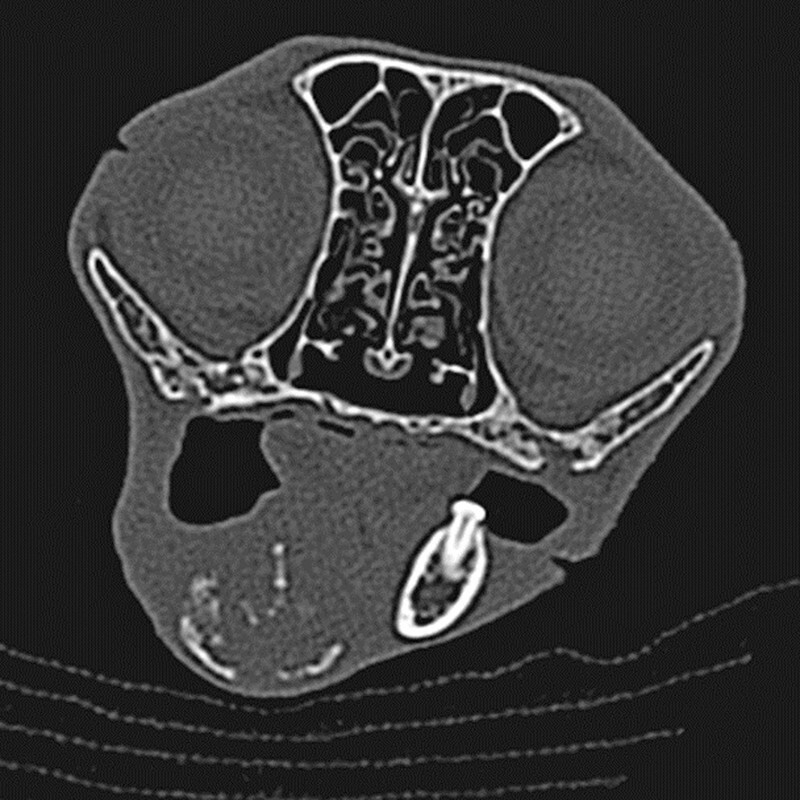

Die Modalität der Wahl bei Neoplasieverdacht ist die Computertomografie (CT) [8] . Als Schichtbildverfahren kann mittels CT eine Aussage über Größe, Lokalisation, Ausmaß, Invasivität der Veränderung und die regionalen Lymphknoten getroffen sowie geeignete Biopsieorte identifiziert werden [8] ( [Abb. 6] ). Die Möglichkeit zur multiplanaren Rekonstruktion stellt eine wichtige Unterstützung für die Planung von Resektionen oder Bestrahlung dar.

Dentale Röntgenaufnahmen sind gut geeignet zur Darstellung kleinerer Kieferabschnitte, ersetzen jedoch bei der diagnostischen Aufarbeitung von oralen Neoplasien nicht die Computertomografie. Die bei felinen Zahnpatienten routinemäßig angefertigten intraoralen Dentalröntgenaufnahmen aller Kieferabschnitte geben einen guten ersten Überblick über die Läsionen. Zahnröntgenaufnahmen sollten deshalb ohne Ausnahme angefertigt werden, auch von nicht zahntragenden Kieferabschnitten, um keine Befunde zu übersehen. Das Röntgenbild eines Patienten mit mandibulär lokalisiertem Plattenepithelkarzinom zeigt bereits die Destruktion des Knochengewebes mit Verlust der Kortikalis, während erst die Computertomografie das Ausmaß und die Ausdehnung der Läsion zeigt ( [Abb. 7] und [8] ).